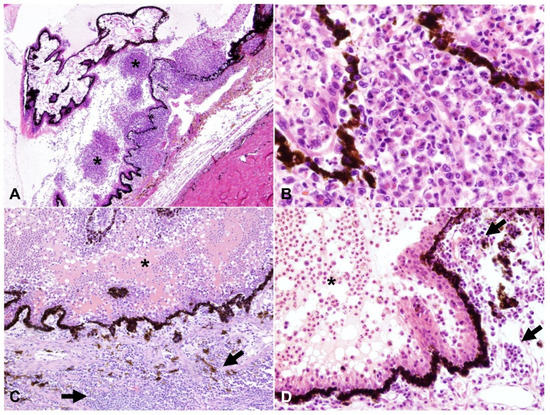

2.3. Detection of Viral Antigen and RNA Via Immunohistochemistry, RNAscope® In Situ Hybridization and RT-qPCR

2.4. Relationship between Type of Inflammation and Detection of Viral Antigen and RNA via Immunohistochemistry, RNAscope® In Situ Hybridization and RT-qPCR